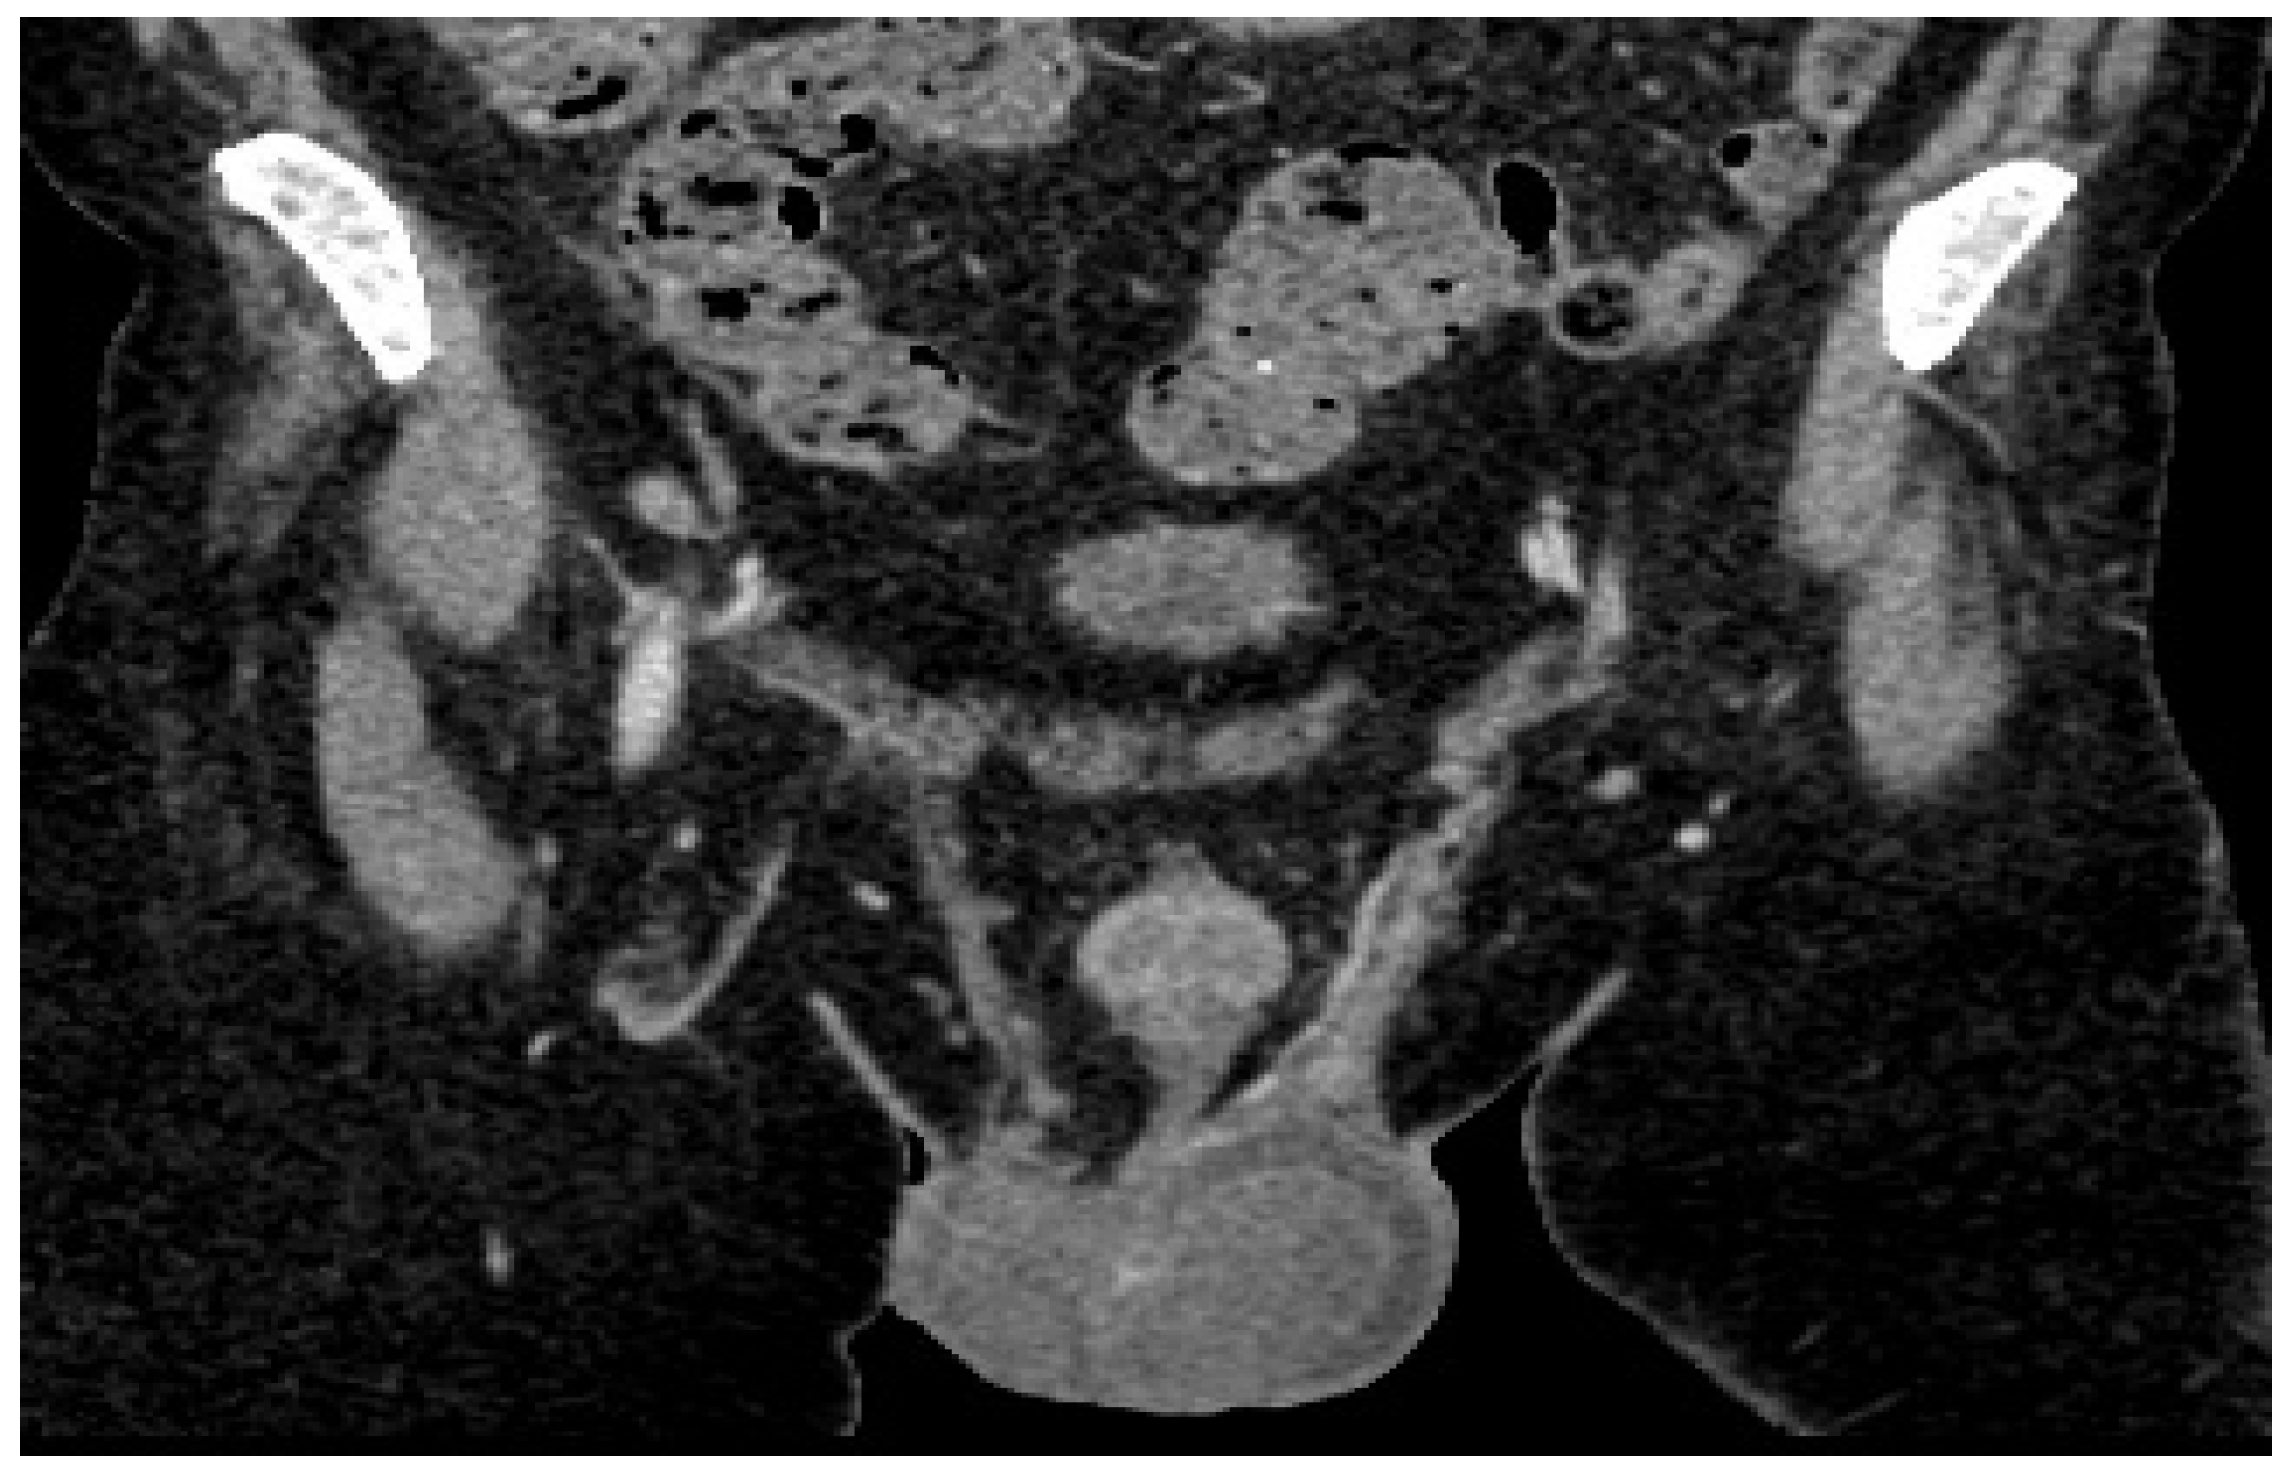

CT examination reveals the left testicle with a regressed dimensional appearance, with current dimensions of 50/40/40 mm vs. 100/60/60 mm and reduced iodophilia compared to the previous examination (Figure 4). Adenopathy along the left testicular vein appeared reduced in size with a maximum diameter of up to 20 mm.

Figure 4. Follow-up post-chemotherapy CT of abdomen and pelvis shows left testicle and adenopathy reduced in size.